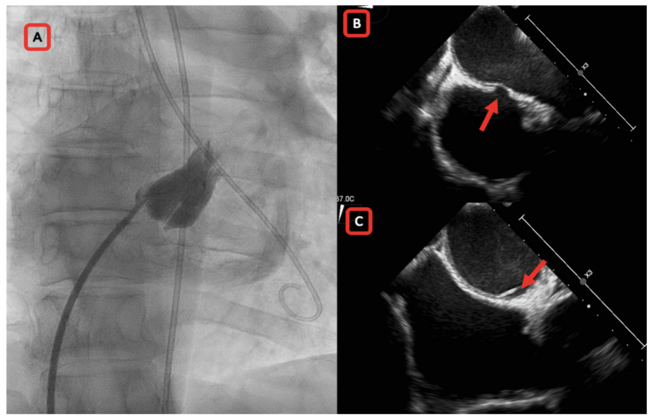

Considering symptomatic severe mitral stenosis and suitable valve anatomy, percutaneous transvenous mitral commissurotomy (PTMC) was planned. Transeptal puncture was done under fluoroscopy guidance using Brockenbrough needle/Mullins 8 Fr dilator combination. Needle’s position in the left atrium (LA) was ascertained with pressure tracing and by withdrawal of bright red blood. To confirm and delineate LA anatomy, on contrast injection via Mullins sheath, an unexpected ovoid shaped, contrast-stained structure was noticed even before the left atrium was filled with contrast (Panel A).

Possibilities considered included stitch phenomenon, interatrial septal dissection, and juxtaposed right atrial appendage. Since LA pressure had been demonstrated prior to injection, inadvertent aortic wall injury was not considered. Unsure of the possible etiology, the dilator and needle were removed. Echocardiography showed no pericardial collection after a waiting period ruling out stitch phenomenon. Computed tomography showed no evidence of juxtaposed right atrium and no aortic wall injury. Transesophageal echocardiography clinched the diagnosis by showing tunnel-like interatrial septal dissection (Panels B and C). Seven days later, the patient underwent successful transseptal puncture and PTMC without complications.